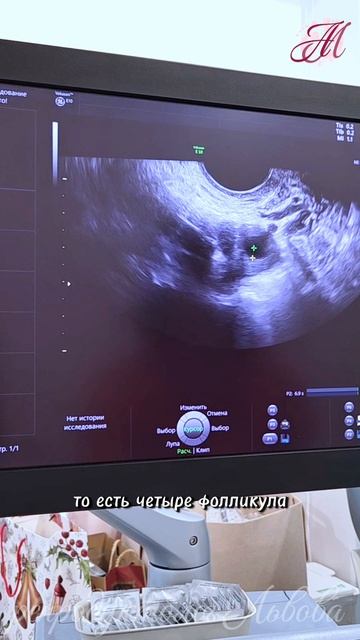

В 2020 году: пациентке 39 лет есть любимый человек но он не хочет детей на данный момент запас хороший на 2 яичника около 10-11 фолликулов АМГ 24 беременностей раньше не было А продолжение уже в 2026.